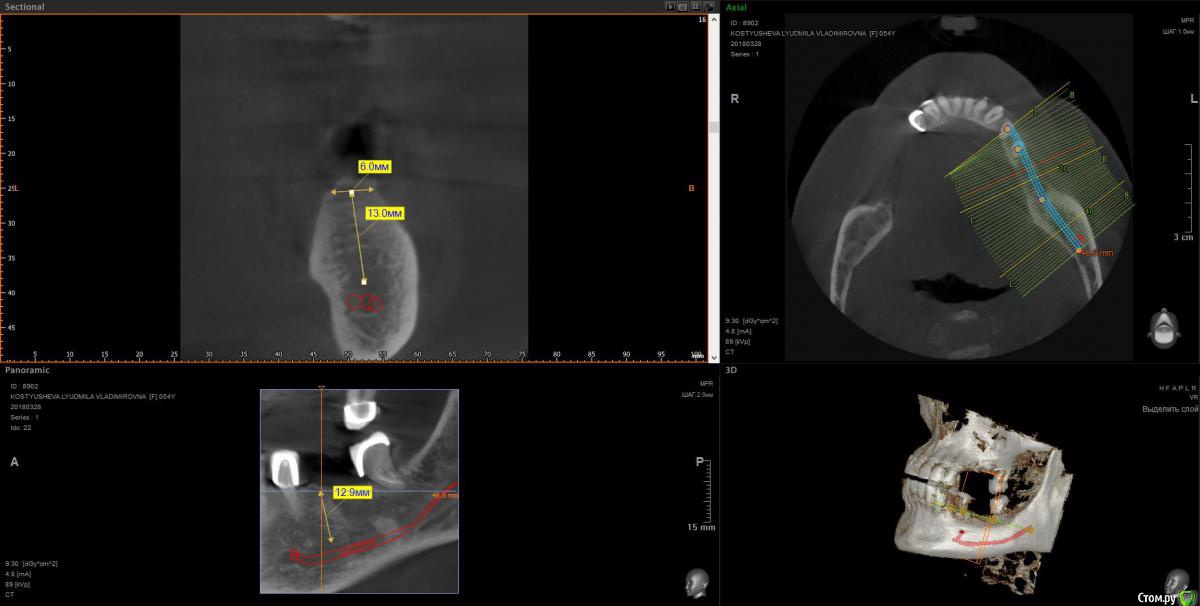

wladdX Опубликовано 9 апреля, 2018 Поделиться Опубликовано 9 апреля, 2018 Несколько скриншотов 2 Ссылка на комментарий

Irouil Опубликовано 10 апреля, 2018 Поделиться Опубликовано 10 апреля, 2018 1. Внизу справа можно имплантироваться, мягкотканную пластику провести нужно будет только 2. В пазухе слева живёт грибок, надо удалять независимо от вида имплантации на верхней челюсти 3. Про зигомы надо ещё КТ самих скул 4. С трефоилом знаком только по наслышке, но он используется (вроде бы) только на нижней челюсти, там необходимости его я не вижу. Коллеги, что знакомы с ним лучше, могут поправить. 1 Ссылка на комментарий

Irouil Опубликовано 10 апреля, 2018 Поделиться Опубликовано 10 апреля, 2018 Спасибо,уважаемые доктора,в пазухе слева дентин.Там пломбировочный материал, возможно искусственный дентин, грибковое тело растет на немА мягкотканная пластика проводится одновременно с установлением имплантов?ДаДля установки имплантов внизу справа сколько их нужно и должны ли они быть меньшего размера из-за атрофии костной ткани?Меньшего чем что? Чем Ваша челюсть? безусловно. В остальном, по моему мнению, установить Вам имплантаты с покрывающими необходимости размерами особых препятствий нет. Нужно два имплантата установить. А импланты внизу слева- сколько их нужно- один или два? С нетерпением жду ответа.Зависит от того, сколько и что будет наверху. 1-2 1 Ссылка на комментарий

Bier Опубликовано 11 апреля, 2018 Поделиться Опубликовано 11 апреля, 2018 я бы думал про установку по паре имплантатов с каждой стороны на каждой челюсти. Слева внизу не вижу состояния зуба, скриншота нет.Внизу справа можно имплантировать, левую пазуху обязательно чистить.О зигомах или трефойле думать рановато, это радикальные вещи уже. Сначала пазуху почистить, потом поставить имплантаты внизу, потом заниматься верхом. 1 Ссылка на комментарий

Irouil Опубликовано 11 апреля, 2018 Поделиться Опубликовано 11 апреля, 2018 (изменено) Зря Вы наркоз не рассматриваете, левую пазуху без него навряд реально вылечить. Нужно КТ полностью смотреть, у меня его качать времени не было, но с большой долей вероятности надо будет через средний носовой ход идти и соустье расширять (если Вы на эндоскопию решитесь, что, безусловно, было бы оптимально), без наркоза это сделать практически невозможно. Там уже интраоперационно можно было бы решить - синусить и имплантироваться сразу или подождав полтора месяца. Если рассматривать классическую имплантацию (6-8 имплантатов на верхнюю челюсть), то синус лифты нужны с обеих сторон, но, опять таки, тут нужно КТ покрутить, может кто из коллег подскажет. Но есть варианты - все на 4 имплантатах, этот метод позволяет обойти верхнечелюстные пазухи, опять таки может кто из коллег подскажет, я им не обладаю. Что касается сроков, то это лучше со своим имплантологом обсуждать, тут зависит больше от Вашей готовности компоновать хирургические этапы. Я бы все по сторонам (правая/левая или наоборот) сделал с перерывом на 4-6 недель между ними и временными протезами, начиная с эндоскопии левой пазухи (ибо она может отложить имплантацию в этой области), но тут (опять и снова) надо полностью КТ глянуть и в рот тоже посмотреть. Изменено 11 апреля, 2018 пользователем Irouil 1 Ссылка на комментарий